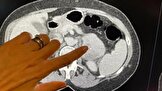

نتیجه یک تحقیق نشان می‌دهد که هوش مصنوعی در درجه‌بندی میزان تهاجمی بودن نوع نادر سرطان از طریق اسکن، تقریباً «دو برابر بهتر» از روش فعلی عمل می‌کند. بر اساس این تحقیق، هوش مصنوعی در تشخیص جزئیات غیرقابل مشاهده با چشم غیرمسلح، ۸۲ درصد دقیق بوده است، در حالی که دقت روش کنونی تجزیه و تحلیل آزمایشگاهی ۴۴ درصد است. محققان بیمارستان رویال مارسدن و موسسه تحقیقات سرطان در بریتانیا می‌گویند که این مزیت هوش مصنوعی می‌تواند درمان سرطان را بهبود بخشد و سالانه هزاران نفر از آن بهره‌مند شوند.